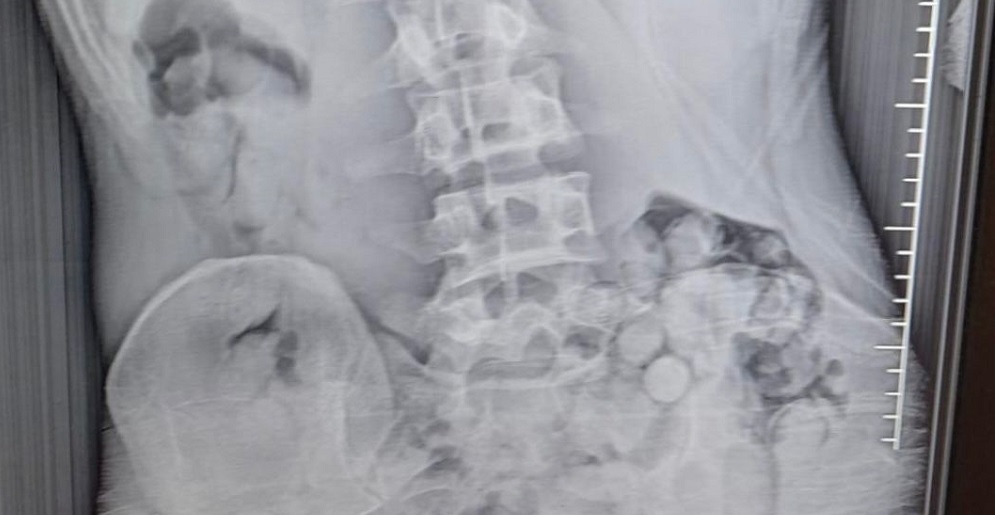

Vücudundan 140 gram uyuşturucu çıktı